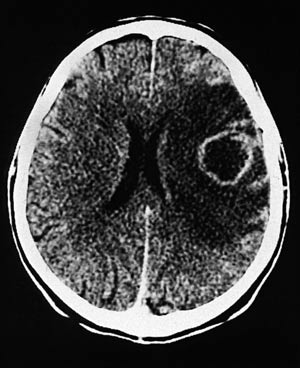

Metastasene er typisk runde i formen, har tilsynelatende god avgrensning til omkringliggende hjernevev, kan ha sentral nekrose og er ofte omgitt av et betydelig ødem. Svulstene har ofte ringoppladning etter kontrast (fig 1).